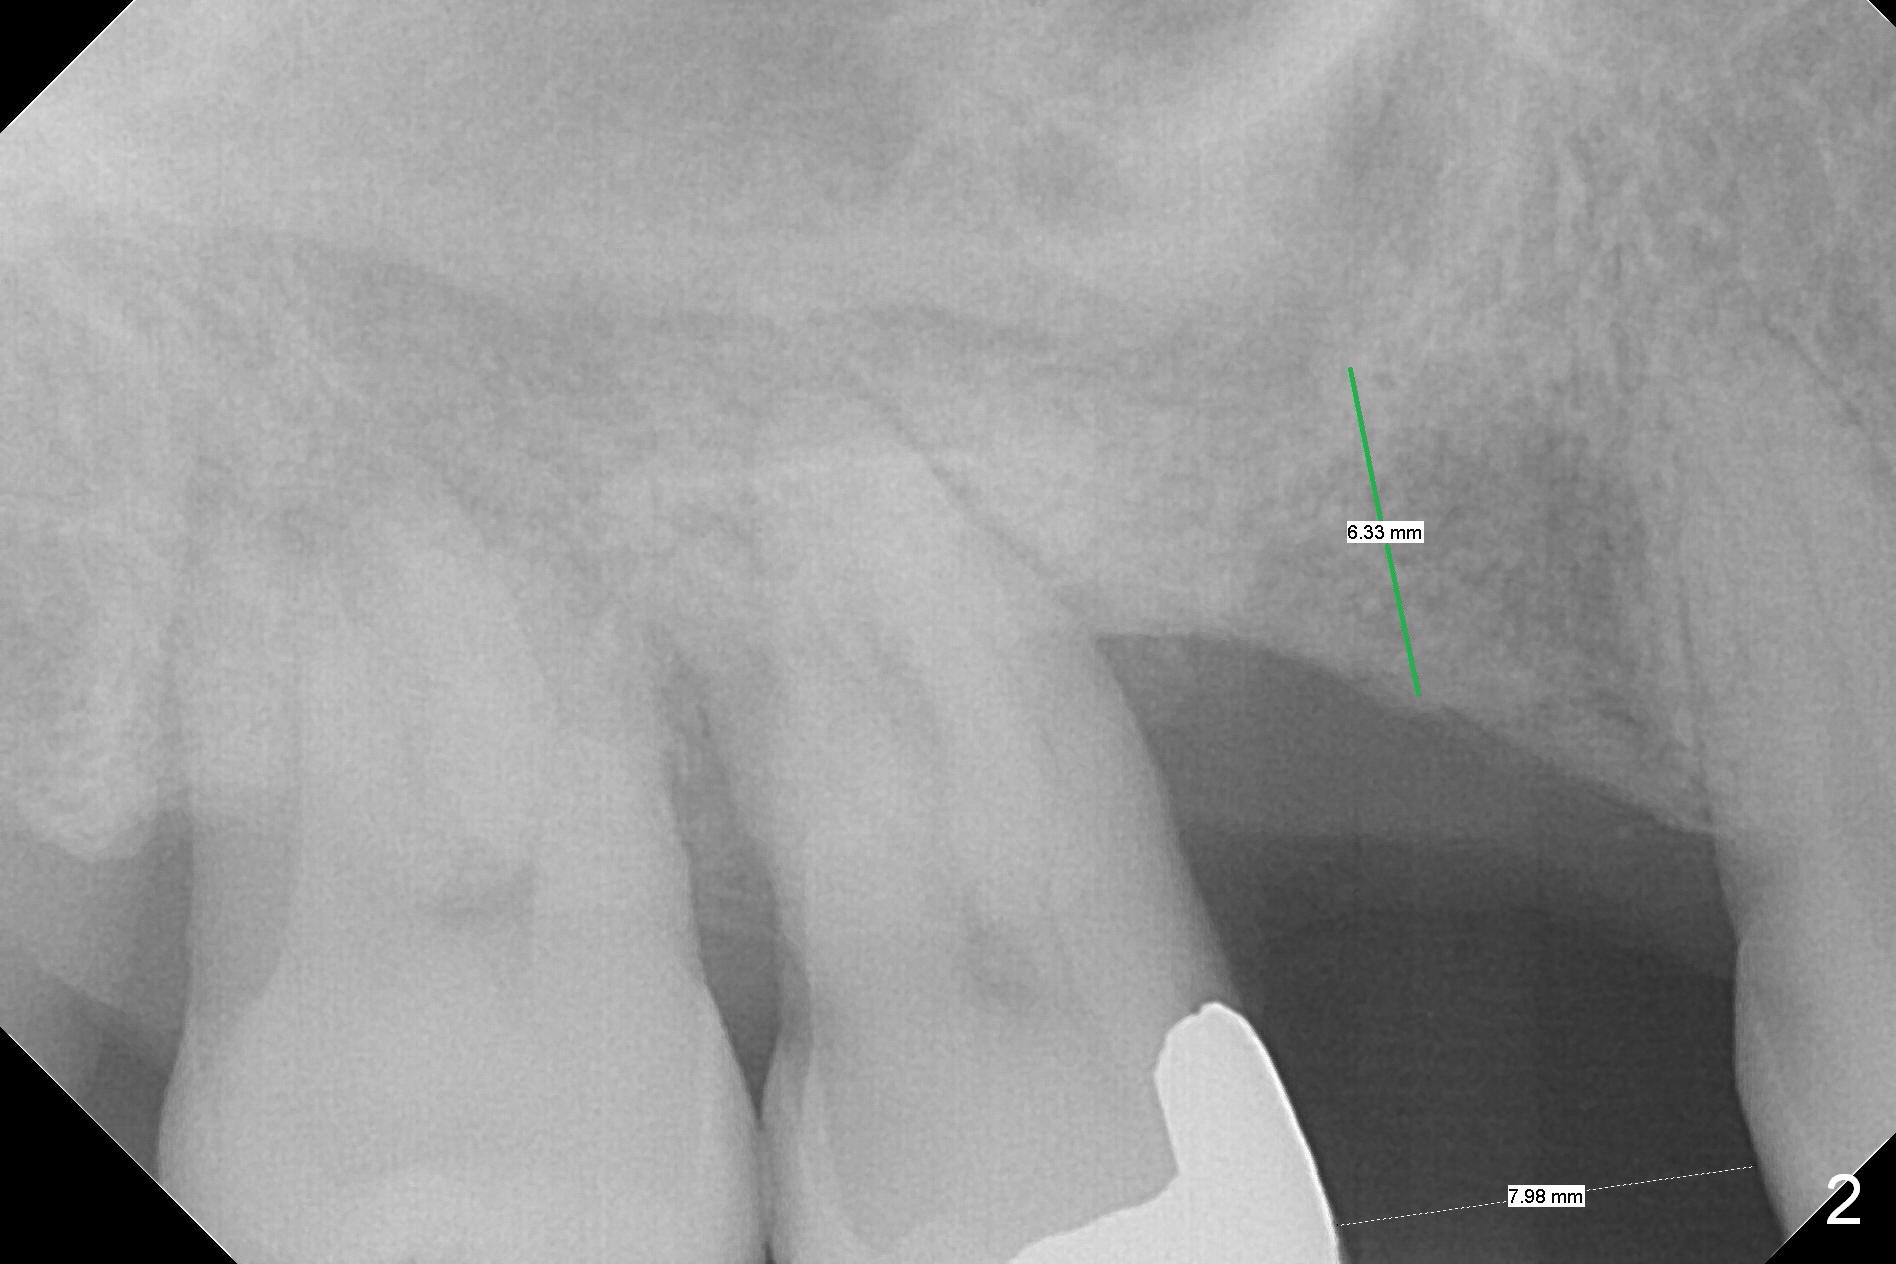

A 53-year-old man wants treatment so that the tooth #2 will not have the fate of the tooth #3. It appears that etiology includes periodontitis and occlusal trauma (Fig.1, 2). The tooth #2 has shifted mesially (Fig.1 ^). The initial drill of DIO Sinus Lift Master Kit will be used for 6 mm (Fig.2), followed by round burs for 7 mm or more. Place PRF and allograft (Metronidazole) before implant placement.